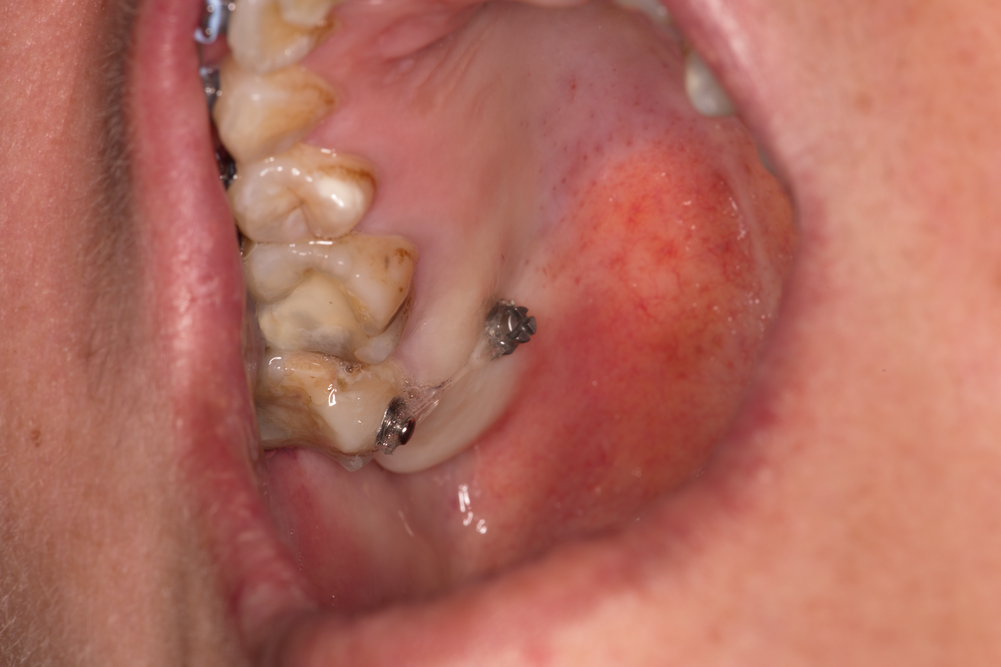

Зъбни импланти с натрупвания на плака и зъбен камък - налице е изразено остро възпаление. В рамките на три дни се формира структурирана зъбна плака, която е особено агресивна - в нейния обем започват да се размножават аеробни и анаеробни микроорганизми, които са основният причнител на зъбния кариес и пародонтита. При периимплантита (възпаление на тъканите около зъбния имплант) положението е същото - наличието на зъбна плака е основен етиологичен фактор. Това налага старателно почистване на надлигавичните елементи както от страна на пациента, така и професионално - от страна на зъболекаря. Колкото е по-грапава една повърхност, толкова повече плака задържа тя и толкова по-трудно става нейното почистване - поради което наистина зъбните импланти с полирана повърхност развиват периимплантити статистически доста по-рядко. Проблемът е че възпалението на околоимплантатните тъкани е полиетиологичен процес - предизвиква се от много и различни фактори, а и зъбна плака е възможно да се задържи дори и върху идеално полирана повърхност. Награпавената имплантатна повърхност е по-добре да бъде разположена интраосално, което в крайна сметка е идеята на дизайна на вътрекостния имплант; при невъзможност за това се налага извършването на костни аугментационни процедури, които изискват допълнително познания и повишено внимание по време на работа. На горната снимка освен това се виждат обилни натрупвания върху цикатризиращите винтове (сулкусформери) - те са полирани, и то при производствени, а не при клинични или лабораторни условия. Зъбната плака и зъбният камък обаче са налице - което е очевиден пропуск от страна на пациента.

При горния клиничен случай се вижда и едно особено неприятно постоперативно усложнение - дехисценцията на оперативната рана. Статистически тя се наблюдава много по-често при поставянето на цикатризиращи винтове върху имплантатната платформа в сравнение с поставянето само на покривни винтове. Тази тенденция се обяснява с формирането на голям брой фиброзни мостчета между срещулежащите ламба - синтезираните съединителнотъканни влакна са механична пречка за отварянето на оперативната рана, което именно представлява дехисценцията. Наличието на гингивални оформители (сулкусформери) пречи на фиксацията на двете раневи повърхности една към друга и вероятността от дехисценция нараства значително. Колкото по-голям е размерът на ламбата и особено дълбочината на отпрепариране, толкова по-вероятно е да се отвори и оперативната рана. Обикновено това се случва на осми - десети ден след поставянето на шевовете - когато започне синтез на съединителна тъкан в дълбочина и съответно придърпване на лигавицата и периоста в трите пространствени иземрения. Значение за дехиценцията има и хирургичната техника при подготовката на ламбото - необходимо е адекватното освобождаване на меките тъкани и срязването на различните мускулни инсерции, които биха могли да придърпват ламбата по време на оздравителния период. Много често се налага така нареченият облекчителен разрез - срязване на периоста в дълбочина, успоредно на основния лигавиченр азрез, при което подвижността на ламбото рязко се увеличава. При ротация на тъканите с цел каквото и да е пластично затваряне на раната вероятността от формиране на дехисценции рязко нараства; това се наблюдава особено често при орални хирурзи с недостатъчен клиничен опит, тъй като те имат повече психологически задръжки по отношение на отпрепарирането на по-големи по размер ламба. Най-добре е при пускане на меките тъкани върху оперативното поле те да застват в желаното пространствено положение пасивно, без да се налага силова адаптация и притискане с инструмент - това гарантира профилактиката на дехисценциите. Така нареченият двуслоен шев адаптира периост срещу периост и това също води до рязко снижаване на честотата на дехисценциите. При всички случаи старателното обшиване с много на брой конци е желателно - в лицево - челюстната област на практика не съществува ограничения в броя на поставените конци на линеен милиметър, тъй като кръвоснабдяването на областта е отлично и исхемизация на тъканите е на практика невъзможна.

При горния случай има съчетание на два неблагоприятни фактора -

недостатъчна орална хигиена

и дехисценция на оперативната рана. При такова положение вероятността от провал

в лечението нараства значително - което и се случи около 3 седмици след

поставянето на имплантите. Съчетаването на два или повече рискови фактора е от

особено значение за всички усложнения в медицината - от най-безобидните до

животозастрашаващите. Това следва да се има предвид при планирането и

оперативното изпълнение на всеки един клиничен случай. Важни са и

постоперативното наблюдение и адекватните грижи за раната. В никакъв случай не

бива да се отпрепарират вторични ламба и да се поставят фиксиращи шевове - това

няма да доведе до корекция и формиране на епителна бариера, а само ще увеличи

площта на дехисценцията и всичко ще изглежда още по-зле след 10 - 14 дни.

Евентуални вторични оперативни намеси могат да се извършват след период от поне

2 месеца - т.е. след окончателното узряване на съединителната тъкан в

оперативното поле и съответно след фиксацията на двете муко - периостални ламба

към подлежащата кост.